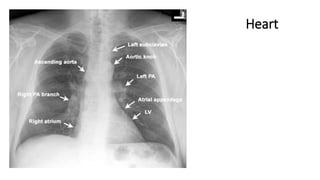

Heart

Cardiothoracic

Index &

Cardiomegaly

Two rules of thumb: CXR evidence of cardiac enlargement.

• On an infant’s AP radiograph the normal cardiothoracic ratio (CTR)

should not exceed 60%1.

• On a child’s PA radiograph the normal CTR can be slightly above

50%, though by the second year it rarely exceeds 50%1